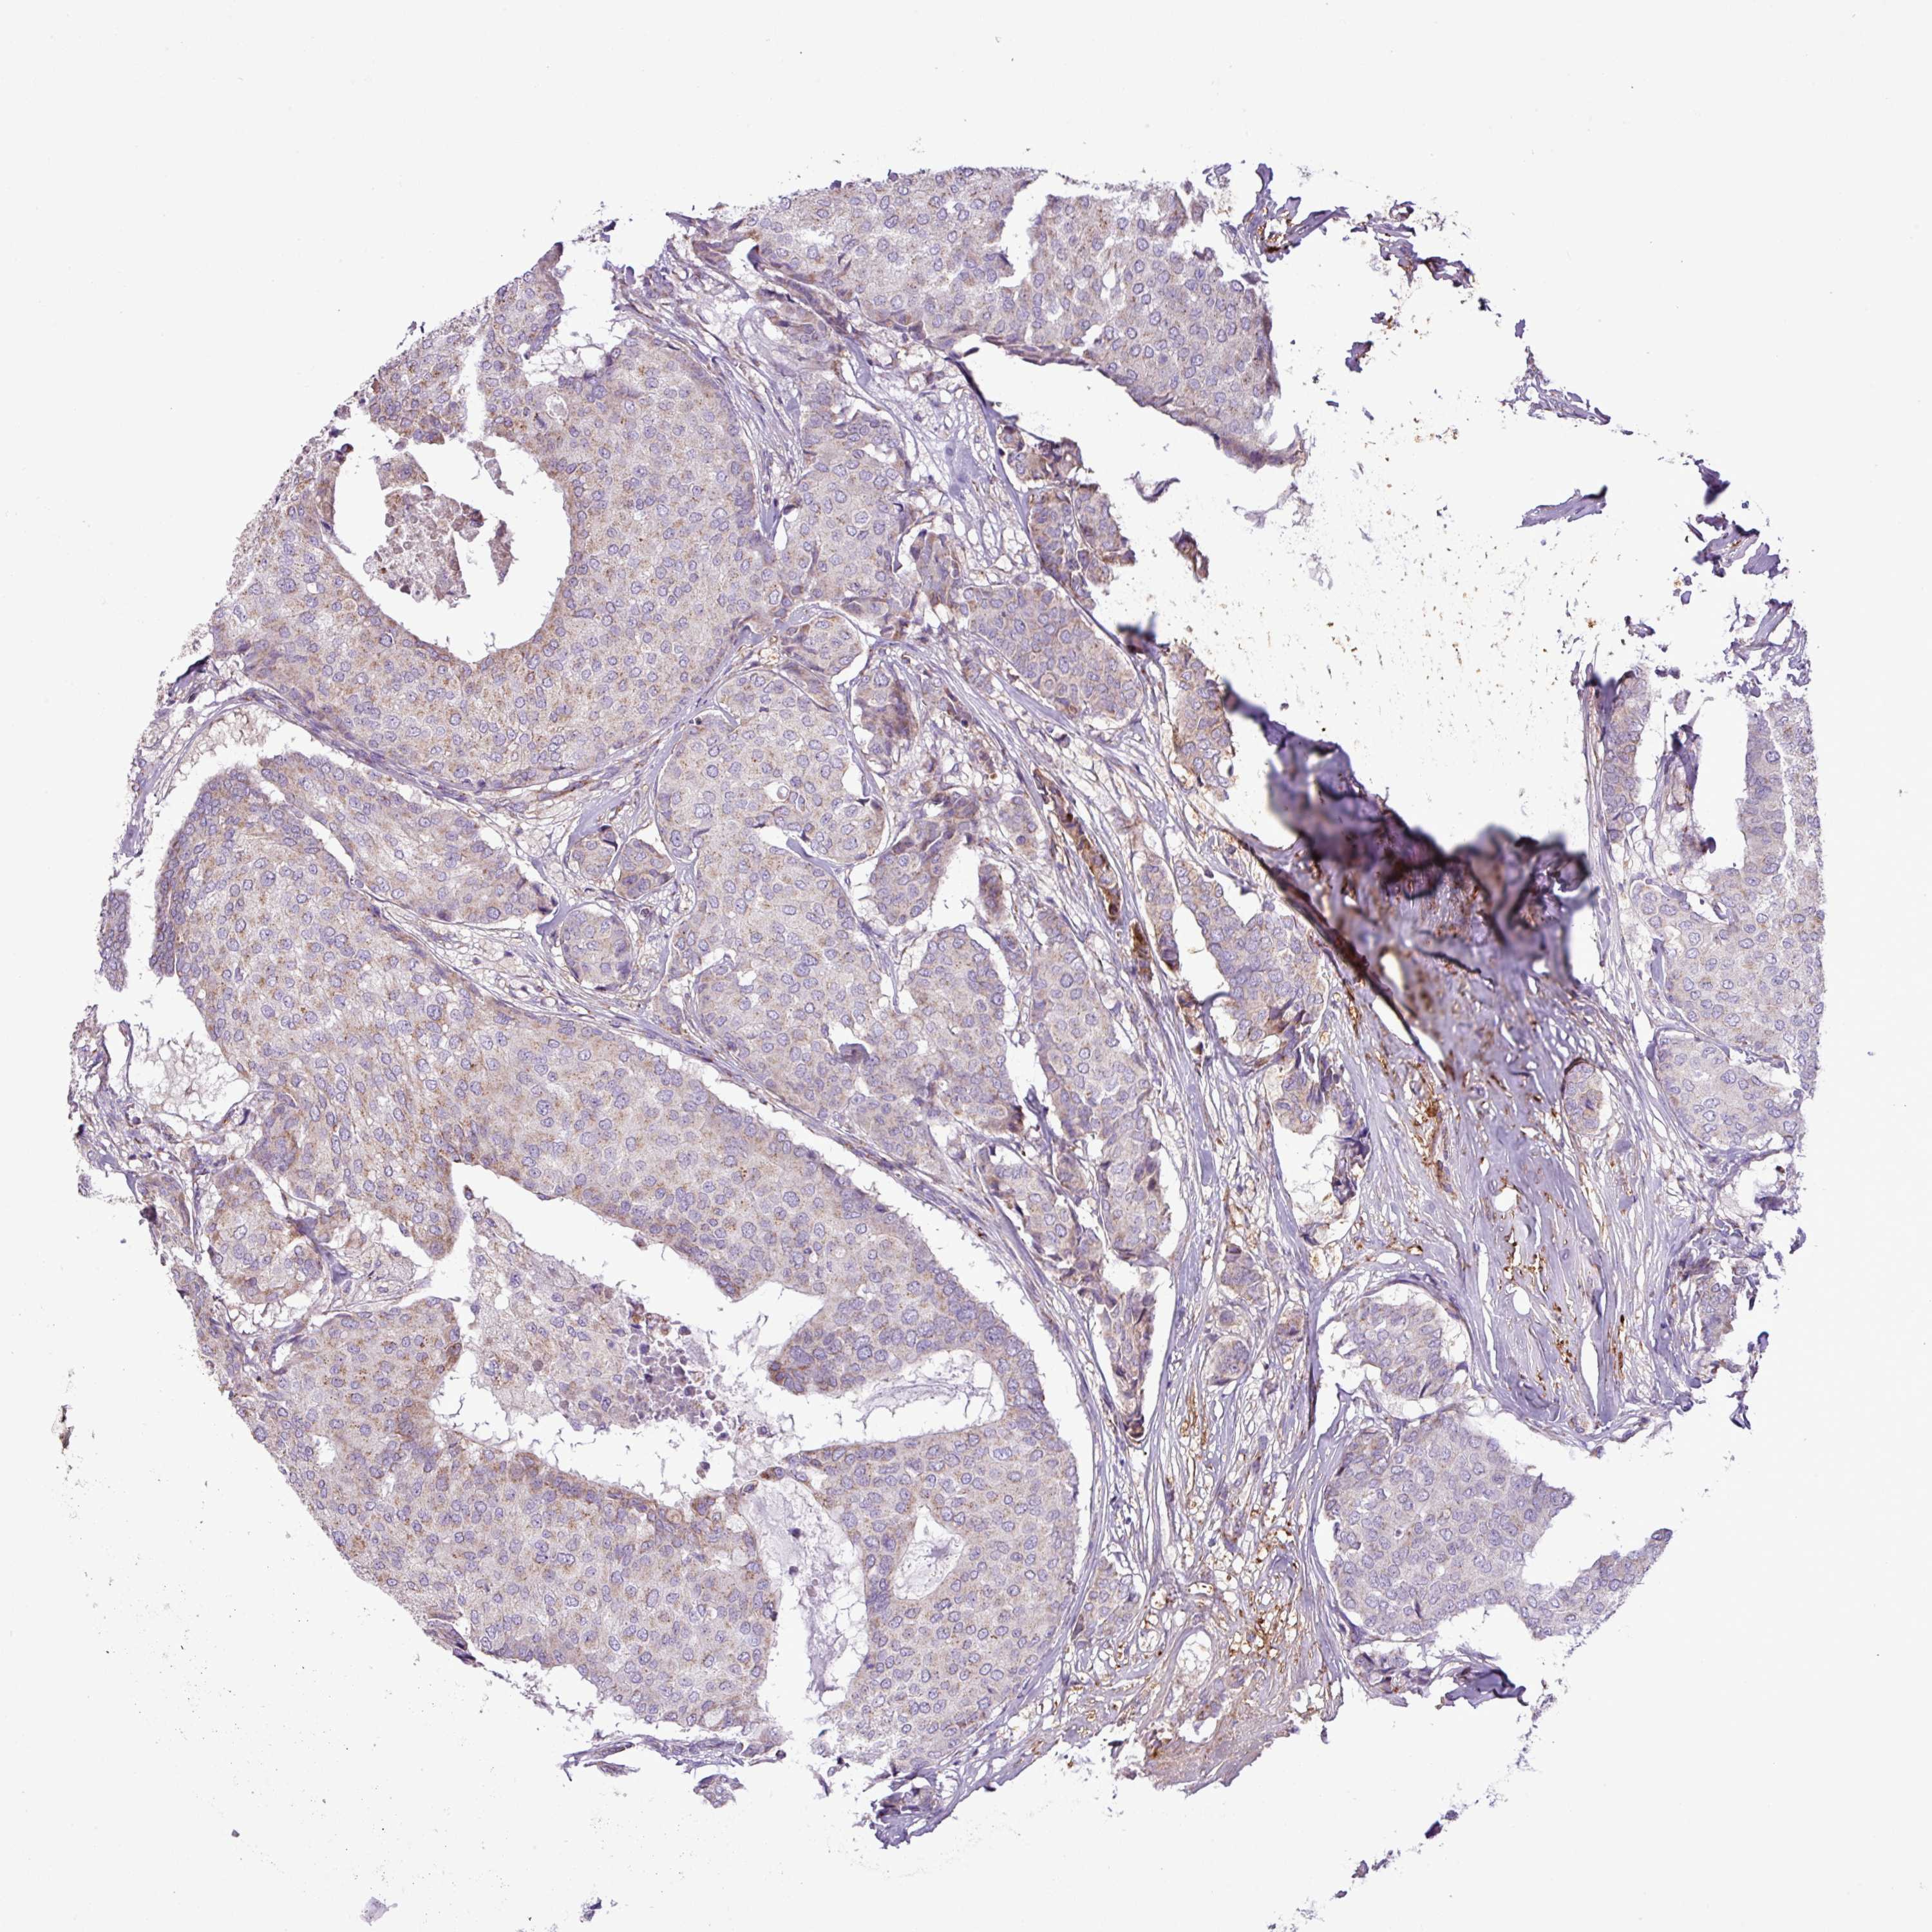

CANCER BREAST CANCER Show tissue menu

BRCA TCGA BRCA VALIDATION PROTEIN EXPRESSION